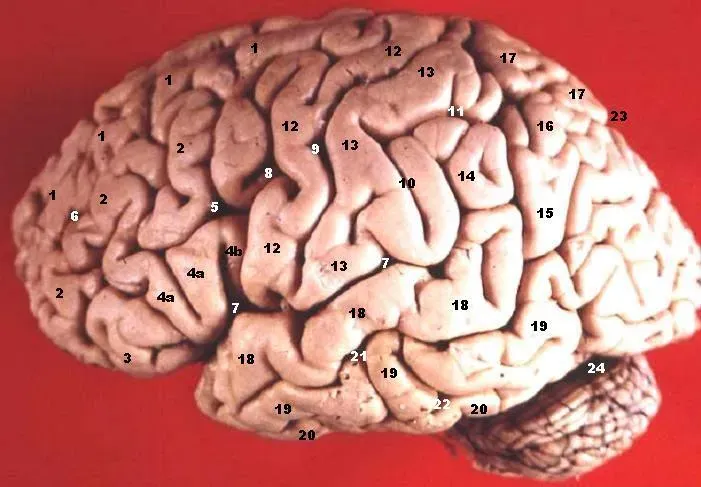

Stop for a second and consider what you’re working with. Your brain holds 86 billion neurons connected by roughly 100 trillion synapses, making it one of the most complex objects in the known universe. That’s not a metaphor. That number is so large it genuinely defies intuition, like trying to count the stars in a clear night sky and realizing you’d never finish in a lifetime.

Think of each synapse as a tiny conversation happening between two brain cells. Now multiply that by 100 trillion. Happening simultaneously. Right now. While you read this sentence. The human brain is arguably the most powerful computer known to humankind, and it acts with extraordinary efficiency and precision. Most of what makes us human resides in the structure and function of this wondrous, multitalented organ.

Here is something I think deserves far more attention than it gets. When you vividly imagine something, your brain activates in patterns remarkably similar to when you actually see that thing in front of you. So how does it tell the difference between the real and the imagined? When you imagine an apple, your brain activity is not that different from when you actually see one. Scientists have now discovered a “reality signal” generated by a region of the brain called the fusiform gyrus, which is then evaluated by another region to determine whether something is real or imagined.

Researchers think that dysfunction of this system could lead to hallucinations, in which people mistake something generated by the brain for something real. Think about that. Hallucinations aren’t random glitches. They may be the result of this very specific reality-checking circuit breaking down. UCL researchers show that the fusiform gyrus emits a signal whose strength determines whether an experience is reported as real or imagined, and this reality signal is interpreted by the anterior insula, which forms part of the prefrontal cortex. The implications for conditions like schizophrenia are staggering.